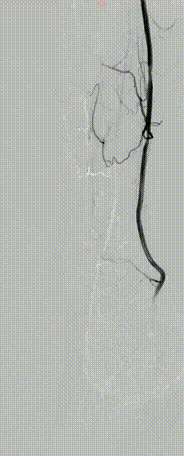

▲造影提示治疗效果良好,成功开通闭塞段。

▲Blades Up模式再次抽吸病变段,股腘动脉管腔获得满意,膝下胫后动脉、足部血流灌注同前,未见明显栓塞。